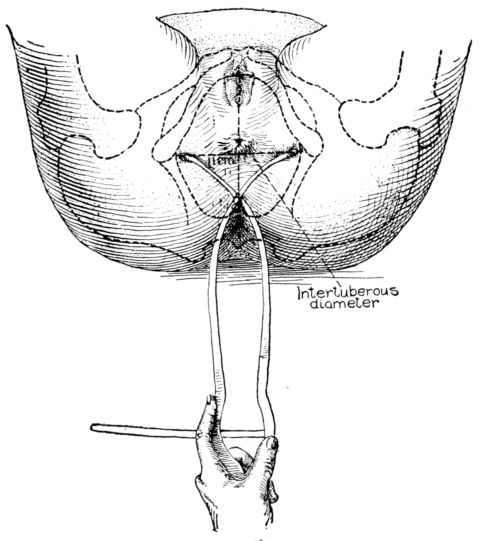

| 9. | Diagram showing method of measuring intertuberous diameter | 29 |

28The most important measurement of the outlet is the intertuberous diameter, the distance between the tuberosities of the ischii. This is the shortest diameter through which the child must pass in the inferior strait, and normally measures something more than 8 centimetres, usually about 11 centimetres. (Fig. 9.)